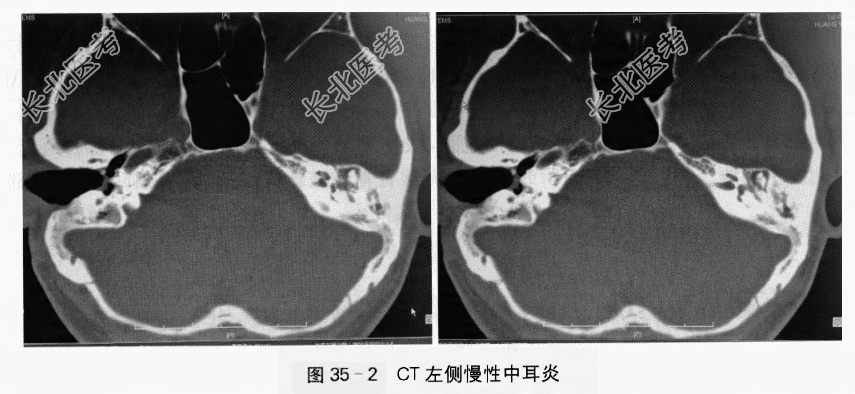

(4)双侧中内耳放大CT提示:左侧乳突气房阻塞性炎症表现、鼓窦和鼓室内低密度影(见图35-2)。